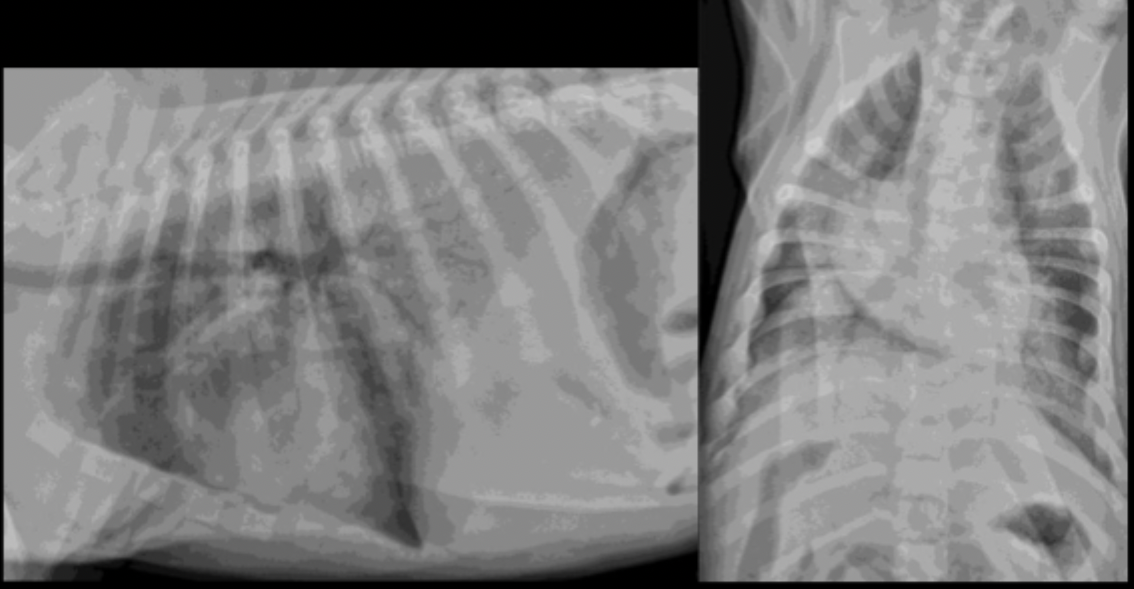

A 9yo MC Cocker Spaniel mix presents for coughing and exercise intolerance. What is the primary pulmonary pattern?

primarily unstructured interstitial pattern

predominantly in the caudodorsal lungs and perihilar region

left worse than right

A 9yo MC Cocker Spaniel mix presents for coughing and exercise intolerance. Your primary pulmonary pattern is unstructured interstital but what other pattern is present?

focally more severe alveolar pattern

A 9yo MC Cocker Spaniel mix presents for coughing and exercise intolerance. What can be seen in this radiograph as far as heart features?

left sided cardiomegaly and left atrial enlargement

A 9yo MC Cocker Spaniel mix presents for coughing and exercise intolerance. What is your primary differential?

cardiogenic edema secondary to left sided congestive heart failure